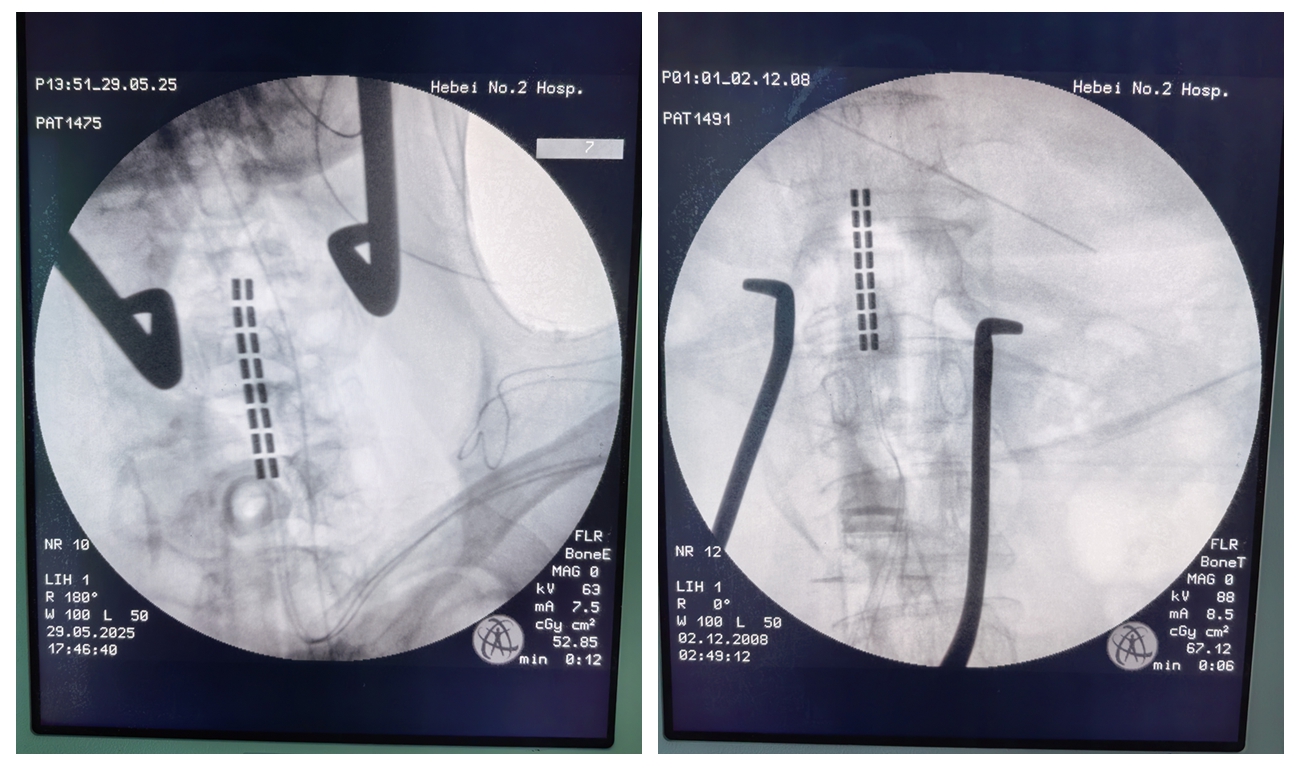

近日,我院神经外科五病区为一例脑出血术后遗留严重痉挛性瘫痪的患者,成功实施脊髓电刺激术,帮助患者打破康复僵局,重获部分运动功能。 患者为51岁男性,脑出血术后半年仍处于朦胧状态,四肢严重痉挛,肌张力显著...